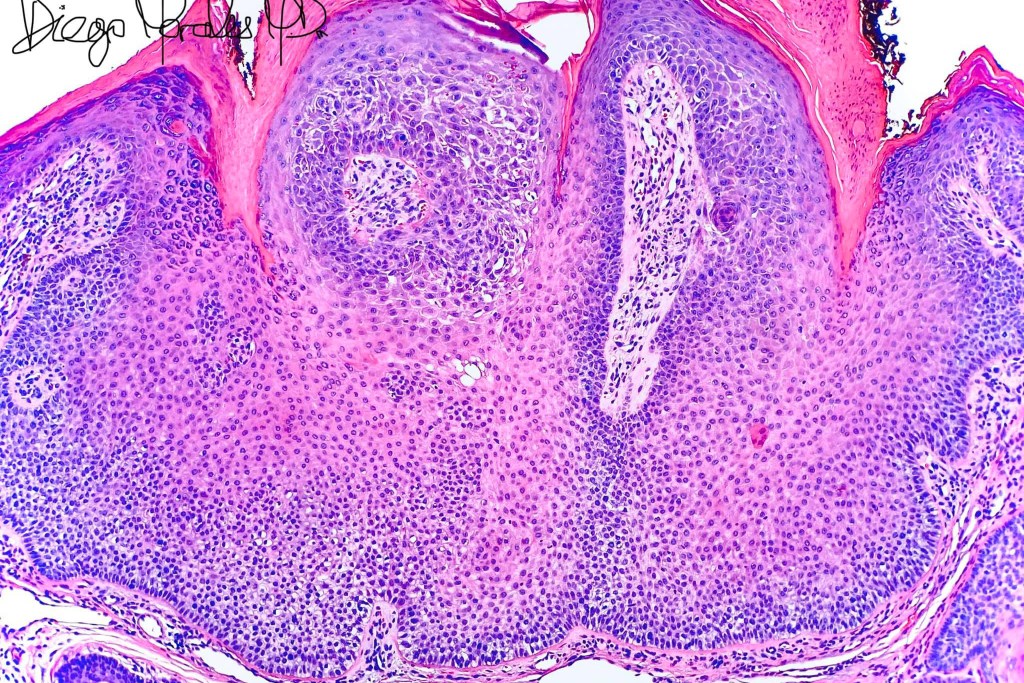

Histologicla features

•Multilobular growth connecting with epidermis & sometimes adjacent follicular external root sheath

•Small epithelial cells with often vacuolated cytoplasm and showing peripheral palisading

•Small nucleoli with vesicular nucleoli

•Rare or no mitoses

•No pleomorphism

•Eosinophilic thick basement membrane

•Overlying hyper- & parakeratosis

•Variable trichilemmal keratinization